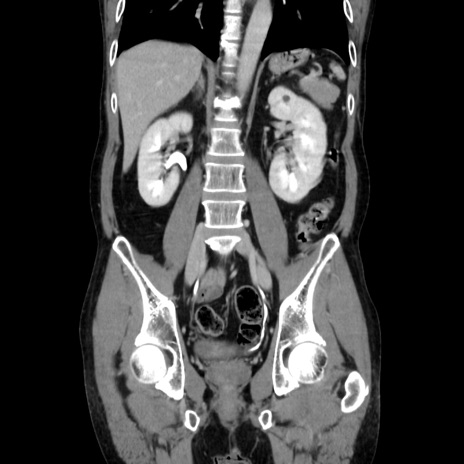

症例37(冠状断像)

【症例】40歳代 男性

【主訴】腹痛

【現病歴】4時間ほど前に電車に乗車中に臍部上より腹痛出現。徐々に増悪し起立困難となり、救急外来受診。生ものは数日食べていない。今朝お雑煮を食べた。

【身体所見】BT 36.8℃、BP 117/84mmHg、HR 91/min、SpO2 97%、苦悶様、腹部:臍上部広範囲圧痛あり、反跳痛±

【データ】WBC 8100、CRP 0.03